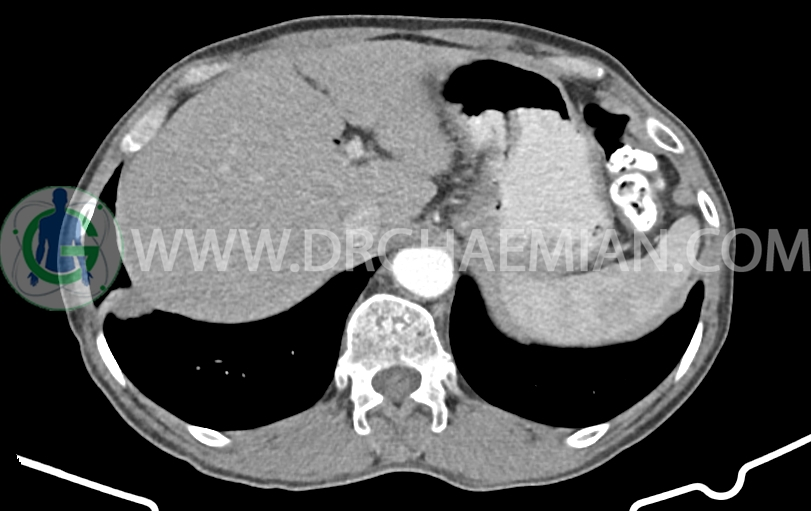

لنف نود به ابعاد mm 14×10 در مجاورت origin SMA دیده می شود. (بدون تغییر نسبت به سی تی اسکن قبلی)

شواهد جراحی ویپل به صورت partial pancratectomy و کوله سیستکتومی و همچنین گاستروژژنوستومی و پانکراتیکوژژنوستومی – هپاتوژژنوستومی مشهود است .

افزایش ضخامت ناحیه کاردیا مشاهده می شود )تطبیق با اندوسکوپی)

MPD دیلاته به قطر 8mm (حاوی استنت می باشد)

body پانکراس کمی کوچک و اتروفیک است